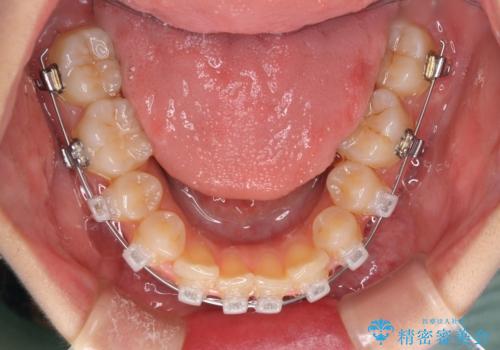

- 矯正装置

- クリアブラケット

抜歯矯正を行ったことで、デコボコが改善されただけでなく、口元も下がったことで口が閉じやすくなりました。